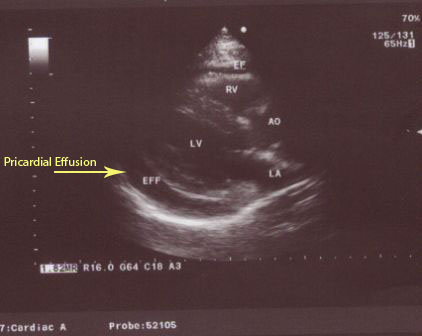

A 62 year old female patient presented with dyspnea to the cardiology unit for which she had ECG and Echocardiography done. She is known to be hypertensive and on β-blocker.

-Echocardiography: moderate pericardial effusion.

We considered this case to have hypothyroidism with pericardial effusion as the sole unusual manifestation which tricked many physicians.

•Pericardial effusion caused by Hypothyroidism may be the sole manifestation.

Pericardial effusion became mild (previously described to be moderate by the same operator)